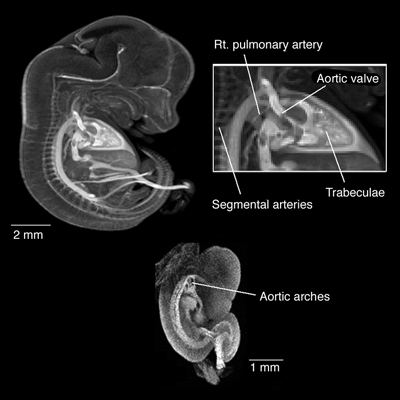

Magnetic resonance image of normal blood vessel and heart development in mouse embryos at 9.5 and 12.5 days.